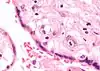

Цитомегаловірус (ЦМВ, ГВЛ-5, Cytomegalovirus hominis) належить до роду Cytomegalovirus, підродини Betaherpesvirinae, родини Herpesviridae. ЦМВ має найбільший геном серед людських герпесвірусів. Наразі відомо троє серотипів цитомегаловірусу людини I, II, III, до яких відносять багато штамів: AD-169, Davis, Towne, TB40/E, Toledo, Merlin, 3157, 6397, 711, 5234, що, можливо, і призводить до різного потенціалу захворюваності[10]. ЦМВ добре зберігається при кімнатній температурі, чутливий до дезрозчинів та нагрівання. ЦМВ зростає в лабораторних умовах лише в культурі людських клітин і, найкраще, в культурі фібробластів. ЦМВ (як й інші β-герпесвіруси) здатні спричиняти характерний феномен цитомегалії — велике збільшення клітин у розмірах із включенням в ядра самих вірусів у вигляді «ока сови».

При локалізованих формах захворювання гігантські клітини знаходять, як правило, в слинних залозах (переважно в привушних залозах, рідше в підщелепних і під'язикових). Формування цитомегалії відмічають в епітелії слинних вивідних проток. В стромі, що їх оточує, відзначають клітинні лімфогістіоплазматичні інфільтрати.